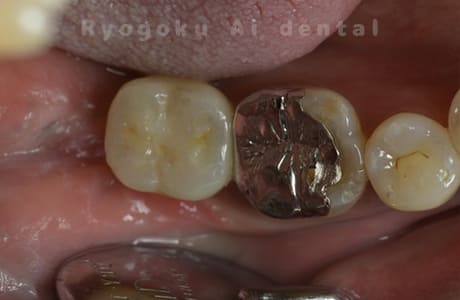

Case12

- 左下7番歯牙破折

-

- 治療内容

- インプラント治療

- 治療費用

- 約600,000円

左下の奥歯が痛いとのことでご来院された患者様です。歯が完全に割れており、保存が不可能であったため、抜歯を行い、その際に骨に変わるお薬を入れ、十分な治癒を待ってからインプラント治療を行いました。経過良好で、大変満足されました。

<リスク・副作用>

治療後、痛みや違和感、出血、腫れなどが出る事があります。喫煙者、糖尿病などの方の場合、歯が生着しない場合があります。